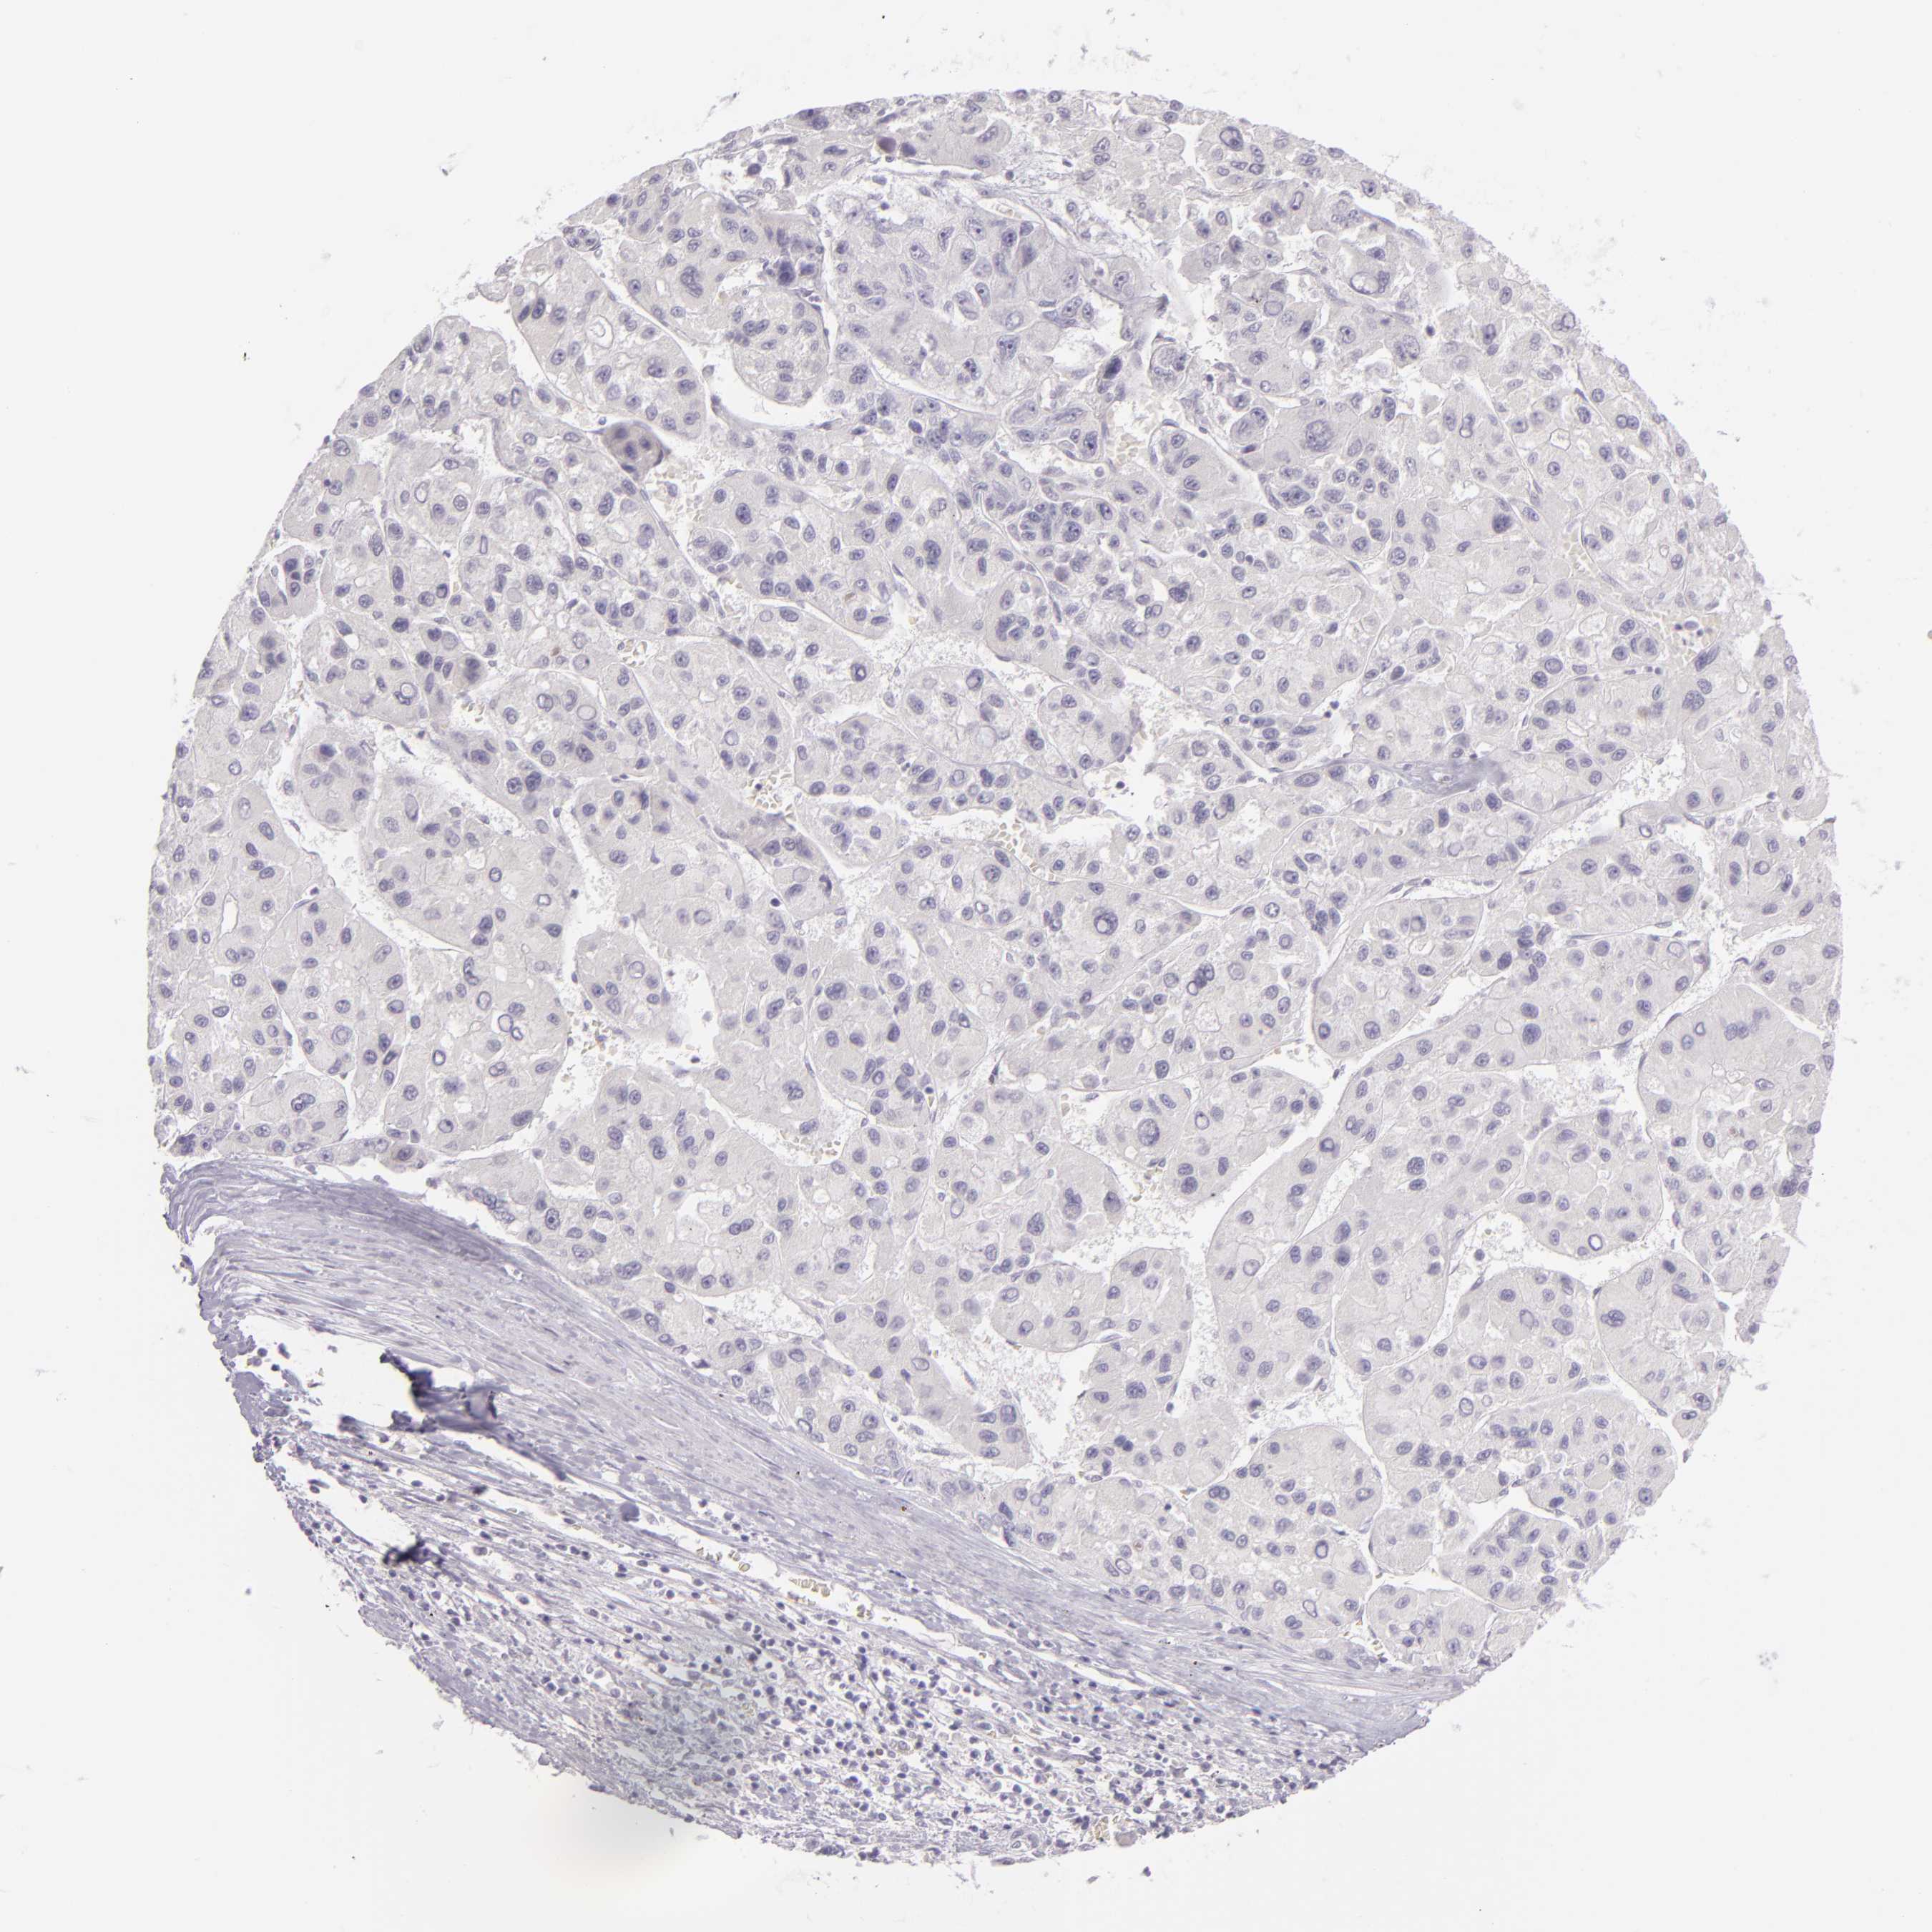

LIVER CANCER - Protein expressioni

A mouse-over function shows sample information and annotation data. Click on an image to view it in a full screen mode. Samples can be filtered based on level of antibody staining by selecting one or several of the following categories: high, medium, low and not detected. The assay and annotation is described here.

Note that samples used for immunohistochemistry by the Human Protein Atlas do not correspond to samples in the TCGA dataset.

Antibody stainingi

Antibody staining in the annotated cell types in the current human tissue is reported as not detected, low, medium, or high, based on conventional immunohistochemistry profiling in selected tissues. This score is based on the combination of the staining intensity and fraction of stained cells.

Each image is clickable and will lead to virtual microscopy that enables deeper exploration of all samples and also displays staining intensity scores, fraction scores and subcellular localization as well as patient and tissue information for each sample.

Antibody HPA001784

Staining

High

Medium

Low

Not detected

Intensity

Strong

Moderate

Weak

Negative

Quantity

>75%

75%-25%

<25%

None

Location

Nuclear

Cytoplasmic/membranous

Cytoplasmic/membranous,nuclear

Carcinoma, Hepatocellular, NOS

Cholangiocarcinoma